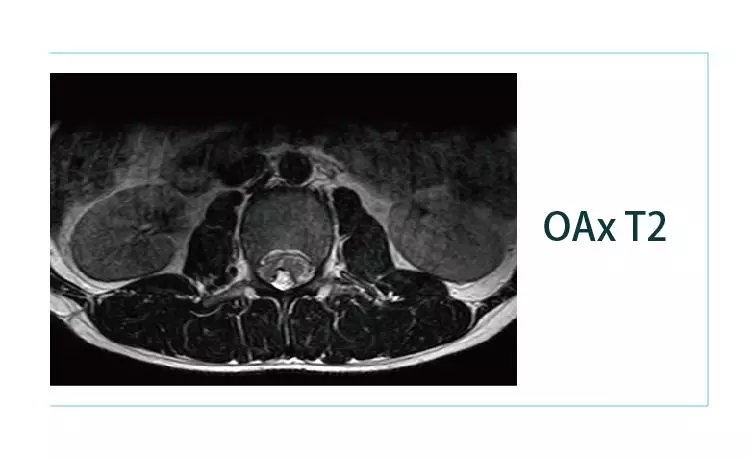

【朗润影像档案】磁共振影像病例分享(编号20190225)

1551142369809397.jpg1551142384228370.jpg